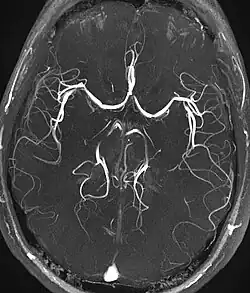

Magnetic resonance angiography

Magnetic resonance angiography (MRA) generates pictures of the arteries to evaluate them for stenosis (abnormal narrowing) or aneurysms (vessel wall dilatations, at risk of rupture). MRA is often used to evaluate the arteries of the neck and brain, the thoracic and abdominal aorta, the renal arteries, and the legs (called a "run-off"). A variety of techniques can be used to generate the pictures, such as administration of a paramagnetic contrast agent (gadolinium) or using a technique known as "flow-related enhancement" (e.g., 2D and 3D time-of-flight sequences), where most of the signal on an image is due to blood that recently moved into that plane (see also FLASH MRI).[53]

Techniques involving phase accumulation (known as phase contrast angiography) can also be used to generate flow velocity maps easily and accurately. Magnetic resonance venography (MRV) is a similar procedure that is used to image veins. In this method, the tissue is now excited inferiorly, while the signal is gathered in the plane immediately superior to the excitation plane—thus imaging the venous blood that recently moved from the excited plane.[54]